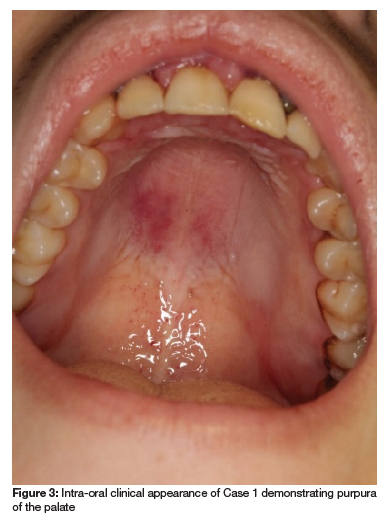

A 22-year-old male patient presented to the University of Pretoria Oral Health Centre (UPOHC), complaining of a painful lower left wisdom tooth (tooth 38), partly impacted and covered by an enlarged operculum. A private dentist had given the patient an appointment to remove the tooth under conscious sedation, but the costs were prohibitive. The attending dentist at the UPOHC noticed anterior marginal gingival bleeding of the maxilla and mandible, and wrongly diagnosed the patient with necrotising gingivitis (Figure 1 and Figure 2). Additional signs, such as purpura of the hard palate (Figure 3), mucosal pallor, skin bruising, and bilateral submandibular lymphadenopathy were noticed, which prompted a consultation by an oral medicine specialist. Further enquiry revealed that the patient recently noticed that his gums bleed easily and his skin bruises easily; he felt tired and was out of breath after walking up the stairs. He presented 2 months earlier to the emergency department of a local hospital with upper respiratory tract infection symptoms. Retrieval of the patient's blood results demonstrates that he already had a reduced red cell count, white cell count, and platelets (See Table I). The patient reported right ear deafness but was otherwise healthy, not using any chronic medication, and had no allergies.